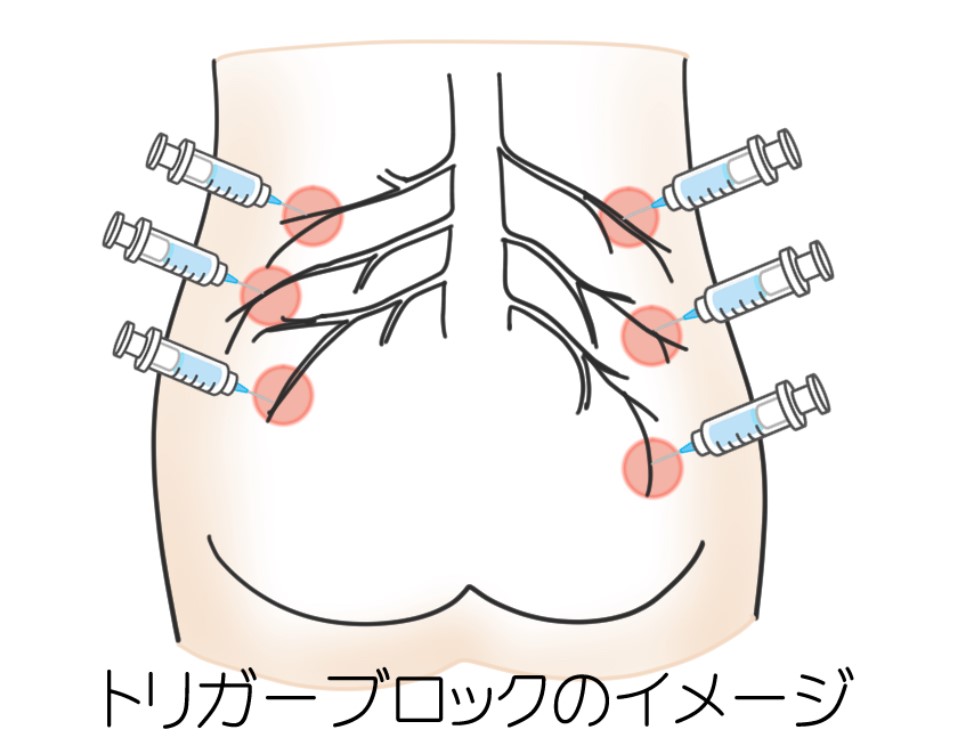

トリガーポイント痛点注射(東洋+西洋医学的治療)

東洋医学の鍼のツボ(痛みの圧痛点)に局麻剤やネオビタカイン注射剤を注射します。週2~3回まで。当院では電気治療や体外衝撃波治療を組み合わせます。

[電気治療・体外衝撃波治療]+[トリガーポイント痛点注射]

| 再診時:注射+物理療法 | 3割負担 約700円 |